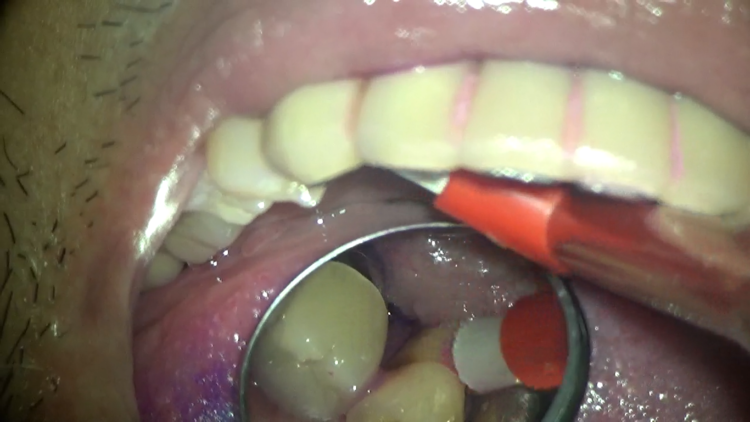

先ずは歯間ブラシを使います。このケースでは表側から歯間ブラシを通していきます。

この時に、ただ真っすぐ歯間ブラシを通すのではなく、角度を変えて、斜めにもしっかりと通していきます。

すると・・・

表側から通しただけなのに、ここまできれいになりました!!